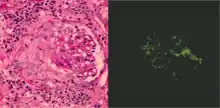

| Photomicrograph of a kidney biopsy from a person with crescentic glomerulonephritis showing prominent fibrocellular crescent formation and moderate mesangial proliferation in a glomerulus. Hematoxylin and eosin stain. | |

Rapidly progressive glomerulonephritis, also known as crescentic GN, is characterised by a rapid, progressive deterioration in kidney function. People with rapidly progressive glomerulonephritis may present with a nephritic syndrome. In management, steroid therapy is sometimes used, although the prognosis remains poor.[9] Three main subtypes are recognised:[4]: 557–558

- Type 1 is Goodpasture syndrome, an autoimmune disease also affecting the lung. In Goodpasture syndrome, IgG antibodies directed against the glomerular basement membrane trigger an inflammatory reaction, causing a nephritic syndrome and the coughing up of blood.[4]: 557 High dose immunosuppression is required (intravenous methylprednisolone) and cyclophosphamide, plus plasmapheresis. Immunohistochemistry staining of tissue specimens shows linear IgG deposits.

- Type 2 is characterised by immune-complex-mediated damage, and may be associated with systemic lupus erythematosus, post-infective glomerulonephritis, IgA nephropathy, and IgA vasculitis.[4]: 558

- Type 3 rapidly progressive glomerulonephritis, also called pauciimmune type, is associated with causes of vascular inflammation including granulomatosis with polyangiitis (GPA) and microscopic polyangiitis. No immune deposits can be seen on staining, however blood tests may be positive for the ANCA antibody.[4]: 558–559

Histopathologically, the majority of glomeruli present "crescents". Formation of crescents is initiated by passage of fibrin into the Bowman space as a result of increased permeability of glomerular basement membrane. Fibrin stimulates the proliferation of endothelial cells of Bowman capsule, and an influx of monocytes. Rapid growing and fibrosis of crescents compresses the capillary loops and decreases the Bowman space, which leads to kidney failure within weeks or months.